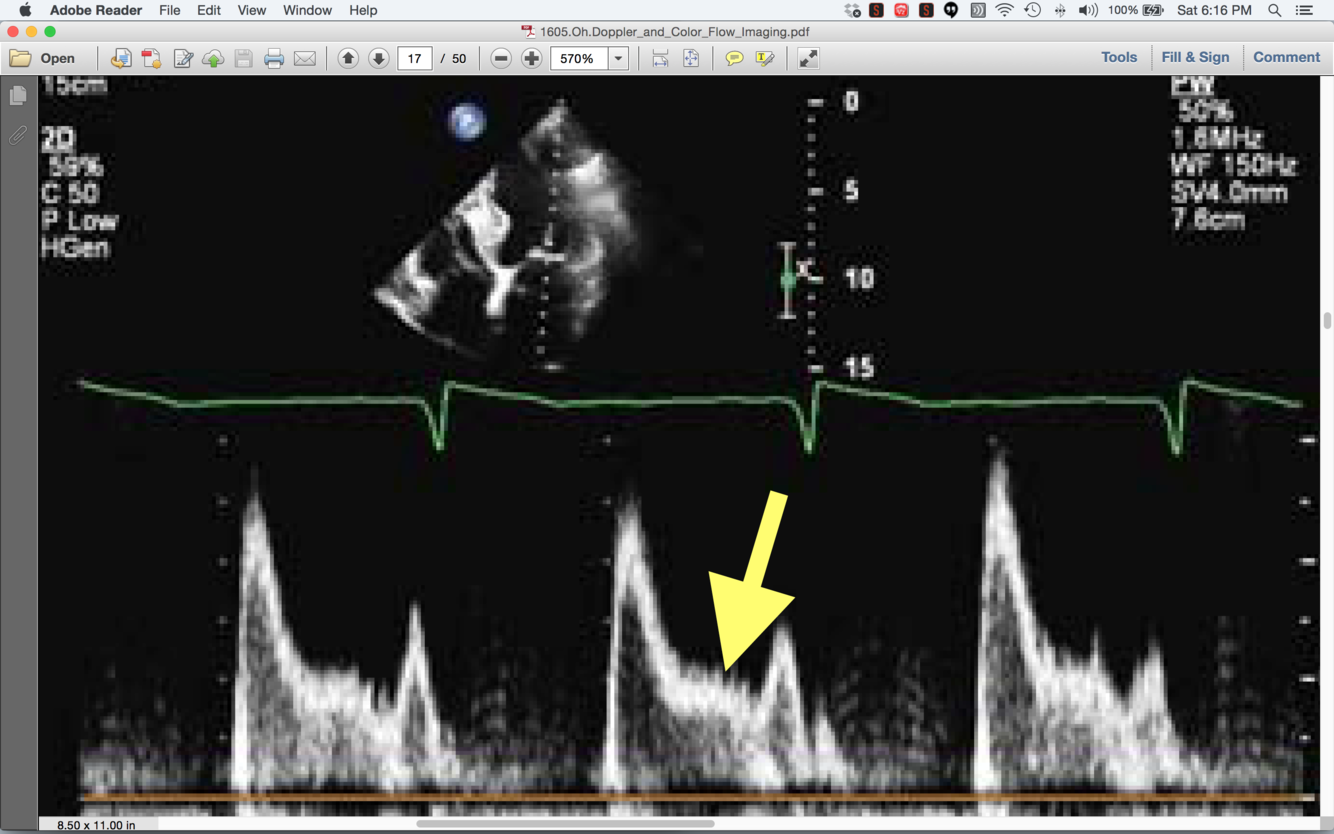

What does this “L-wave” mean? (hint- happens a LOT in afib)

delayed relaxation and increased filling pressures